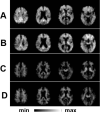

In this grand rounds, we focus on development, validation, and application of neuroimaging biomarkers for Parkinson disease (PD). We cover whether such biomarkers can be used to identify presymptomatic individuals (probably yes), provide a measure of PD severity (in a limited fashion, but frequently done poorly), investigate pathophysiology of parkinsonian disorders (yes, if done carefully), play a role in differential diagnosis of parkinsonism (not well), and investigate pathology underlying cognitive impairment (yes, in conjunction with postmortem data). Along the way, we clarify several issues about definitions of biomarkers and surrogate endpoints. The goal of this lecture is to provide a basis for interpreting current literature and newly proposed clinical tools in PD. In the end, one should be able to critically distinguish fact from fantasy.